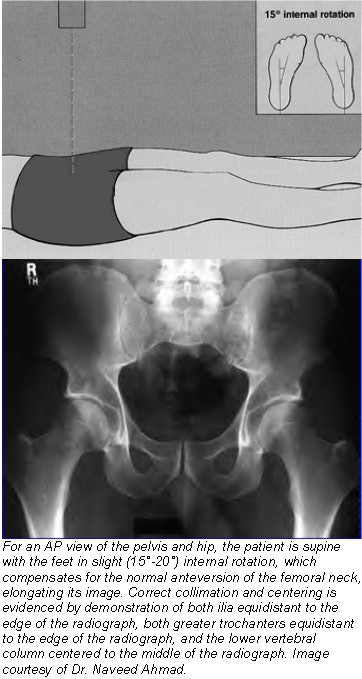

- The feet are placed in approximately 15°-20° of internal (medial) rotation. This is done to overcome the normal anteversion of the femoral necks and to place their longitudinal axes parallel to the film. The heels should be 8-10 inches (20-24 cm) apart.

- Correct collimation and centering is evidenced by demonstration of both ilia equidistant to the edge of the radiograph, both greater trochanters equidistant to the edge of the radiograph, and the lower vertebral column centered to the middle of the radiograph.

![]() |